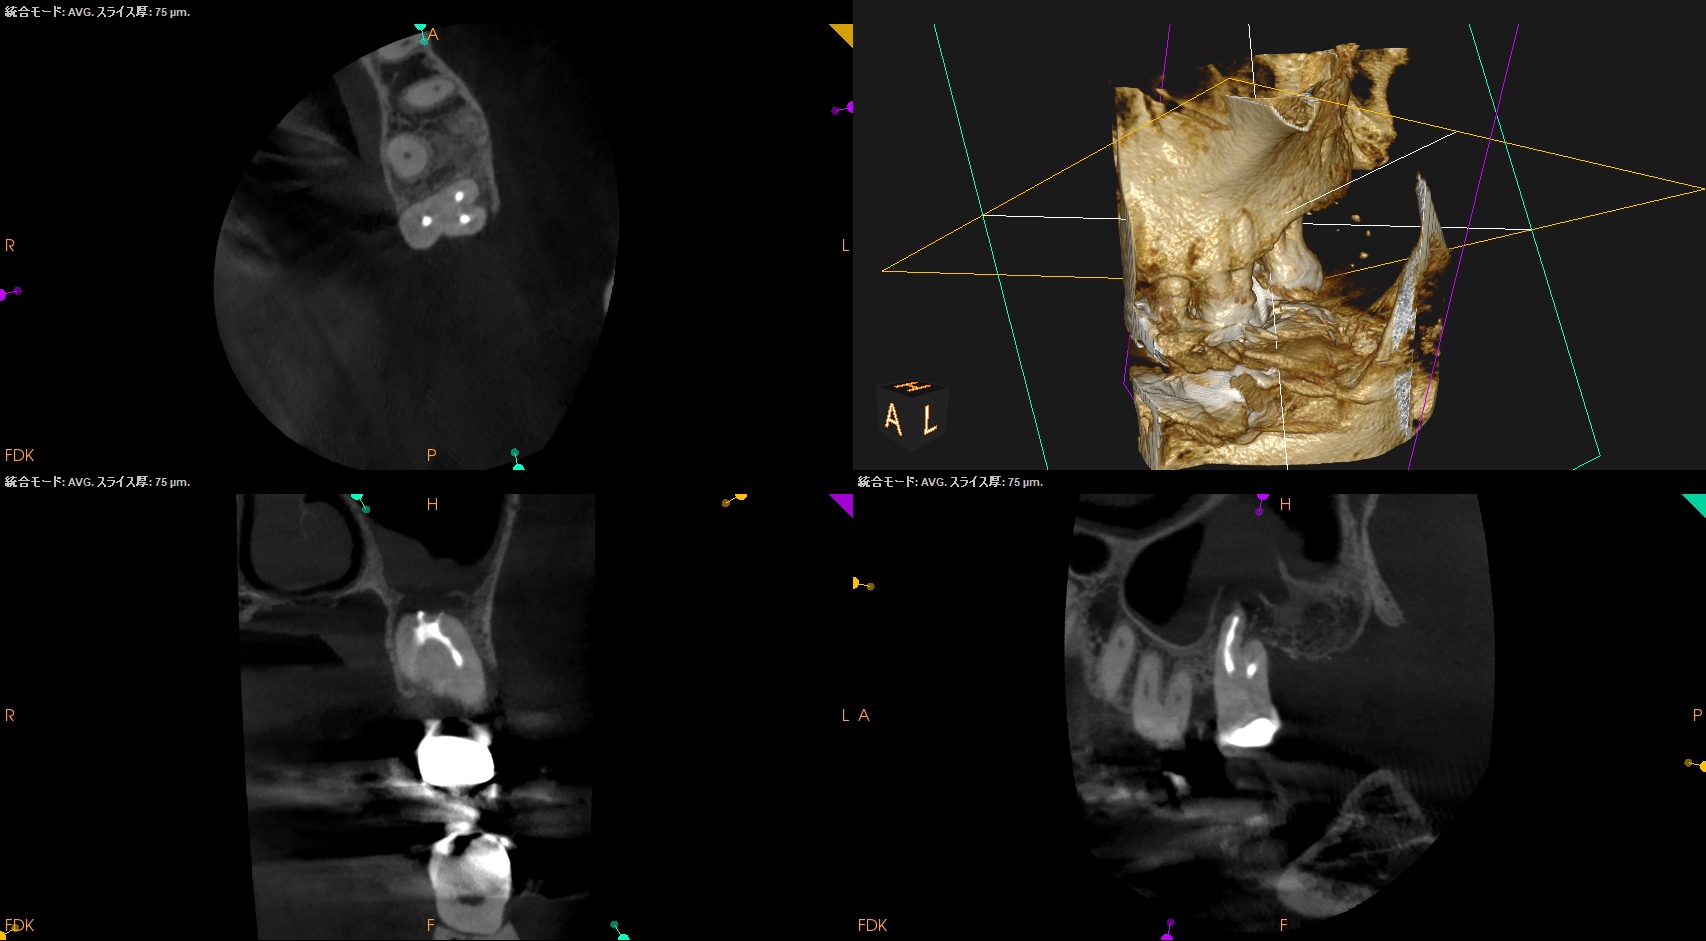

CBCT(2024.7.31)

MB

DB

P

根尖病変があり、上顎洞炎を呈している。

根管治療が必要だ。